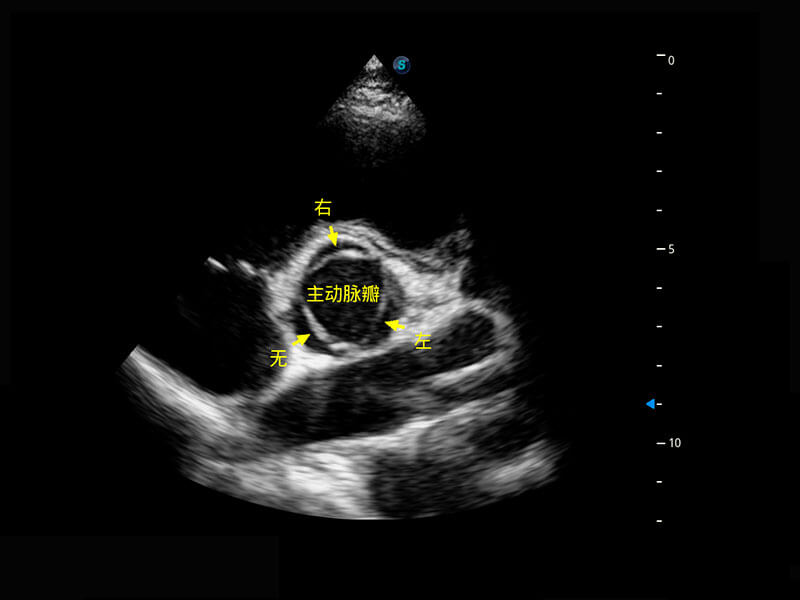

P60搭载一系列胎儿心脏成像技术,实现精细的胎儿心脏评估。

四腔切面

右室双出口